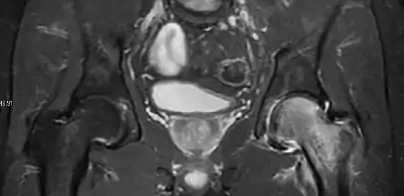

Magnetic resonance imaging

Many pathological conditions of the hip are detected early by MRI due to its high soft tissue resolution and sensitivity. Its accuracy in studying acute hip pain in children has proved to be superior to ultrasound and plan film radiography. However, MRI accessibility and the need of sedation relegate its use to selected cases in which diagnosis is not clear with less demanding techniques. These include differentiating transient synovitis from a septic arthritis or osteomyelitis, diagnosis of inflammatory joint disease or bone tumors, and early detection and follow-up of Perthes disease.[1]

In adults, MRI is currently playing a definite role in the assessment of osteoarthritis. Although traditionally belonging to the arena of radiographs, the role of MRI has been stressed after the term femoral acetabular impingement was coined in 2003. Growing interest has been focused in accurate diagnosis of the acetabular and femoral morphological abnormalities that may lead to early osteoarthritis.[1]

MR imaging is considered paramount to these objectives, mainly when surgery is considered, due to the ability of MRI to portray the whole section of the femoral neck surface, as well as to image the labrum and articular cartilage.[1]

Most of the angles and measurements described in the plain radiograph section can be accurately reproduced on MRI. In addition, the superiority of MRI resolution with intra-articular contrast allows detection of labral and chondral abnormalities that may influence the choice of medical, percutaneous, or surgical management (Figure 9).[1]

Figure 9: